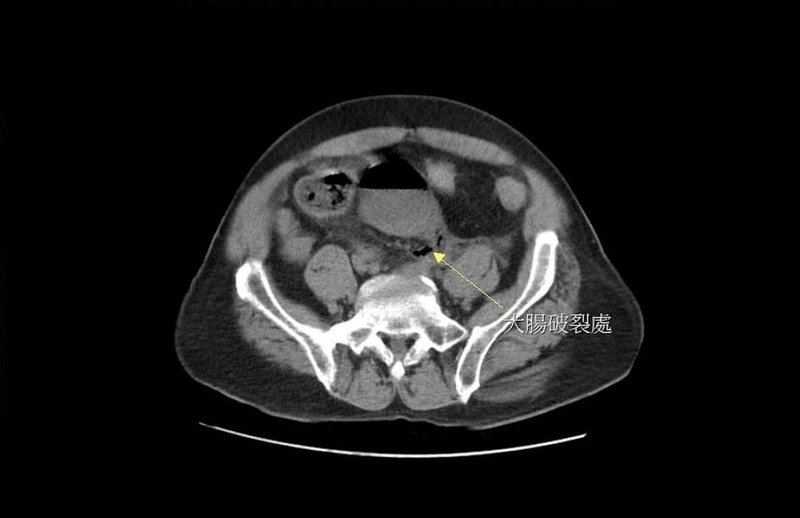

大千醫院指出,黃男日前又因連續3天無法解便而自行灌腸,發現沒有效果,於是改用更長的管子,把瀉藥送入直腸深處灌腸,突然引發劇痛,被家人緊急送至醫院急診,經電腦斷層掃描後發現,男子直腸上端處有巨大破洞,糞水隨著破洞流進腹腔,引發嚴重腹膜炎。

大千醫院外科部主任馮啟彥緊急進行腹腔鏡手術,術中發現破洞位於直腸上端靠近乙狀結腸的轉彎處,直徑約2公分,研判應是太用力灌腸造成的腸道破裂,也讓大量的宿便流進腹腔,才會引發嚴重的腹膜炎。所幸黃男術後順利康復,但也嚇得直呼「再也不敢自己隨意灌腸了」。